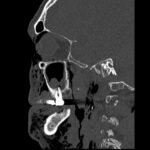

Subcutaneous emphysema (SE) is a rare but significant complication following dental procedures characterized by the presence of air in the subcutaneous tissue. This case report presents a 67-year-old male who developed right-sided facial swelling after tooth extraction, a procedure executed with high-power dental tools. Clinical findings included facial swelling and crepitus with no lip involvement, differentiating SE from an allergic reaction and hematoma. Diagnostic imaging through computed tomography (CT) and chest X-ray confirmed SE, showing diffuse subcutaneous air in facial and neck soft tissues. Initial management in the emergency department (ED) involved administration of antihistamines, corticosteroids, antibiotics, and otolaryngology (ENT) consultation with close monitoring for airway compromise. This case underscores the importance of including SE in differential diagnoses for post-dental procedure swelling, the effectiveness of CT imaging in SE identification, and the importance of early detection and treatment to prevent severe complications like respiratory and cardiac issues.